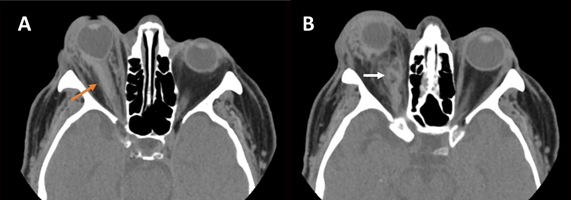

Figure 1 Ocular compartment syndrome secondary to trauma in the right eye. Axial sections of non-contrast-enhanced orbital CT showing A) marked right proptosis with deformity of the posterior pole known as “guitar pick” sign, as well as elongation of the ipsilateral optic nerve, with perineural hemorrhage (orange arrow). Image B shows retroocular hemorrhage in the medial aspect of the intraconal space (white arrow).

Clinically, patients present a decreased visual acuity, with a tense eyeball, increased intraocular pressure, proptosis, relative afferent pupillary defect, and restriction in eye movements. If intraocular pressure increases sufficiently, it can decrease perfusion of the retina and the optic nerve, leading to ischemia and permanent vision loss. The test of choice is CT, where proptosis of the affected eyeball is observed, as well as a deformity of its posterior pole with an angle less than 130º, known as the “guitar pick” sign. This angle results from two tangential lines, one to the medial wall of the eyeball and the other to the lateral wall, converging at the insertion of the optic nerve. If this angle is less than 120º it indicates severe proptosis with an unfavorable prognosis.4,5

Stretching of the optic nerve, a smaller caliber superior ophthalmic vein in the affected eye, and the presence of retrobulbar hemorrhage can also be observed. There are no significant differences in the size and shape of the extraocular muscles. Given its association with a history of trauma, patients may have intracranial hemorrhages and facial fractures. Likewise, ocular ultrasound can be useful in identifying signs that suggest the existence of an ocular compartment syndrome, such as the “guitar pick” sign, or the assessment of ocular vascularization by the Doppler study.6